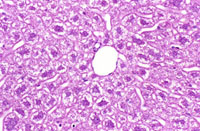

Perfusion fixation of the liver from a non-fasted mouse. Fixative was 10% NBF.